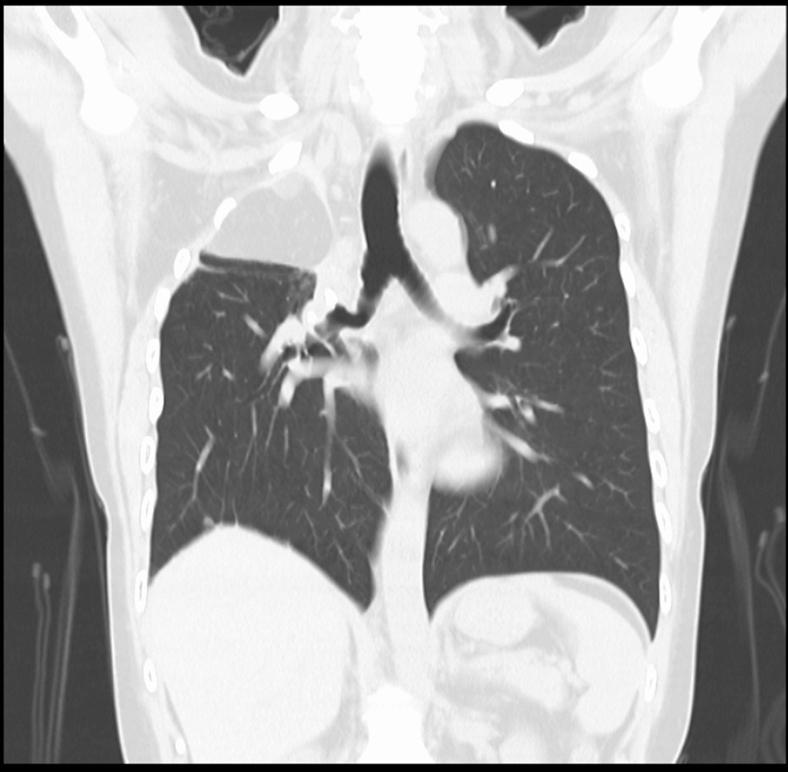

Free omentum filling for bronchopleural fistula after lung resection.

Division of Thoracic Surgery, Department of Thoracic Surgery, Kurashiki Central Hospital, Kurashiki, Japan.

JTCVS Tech. 2024 Apr 10;25:247-249. doi: 10.1016/j.xjtc.2024.03.022. eCollection 2024 Jun.

Free omentum filling for bronchopleural fistula after lung resection.游离大网膜填充术治疗肺切除术后支气管胸膜瘘